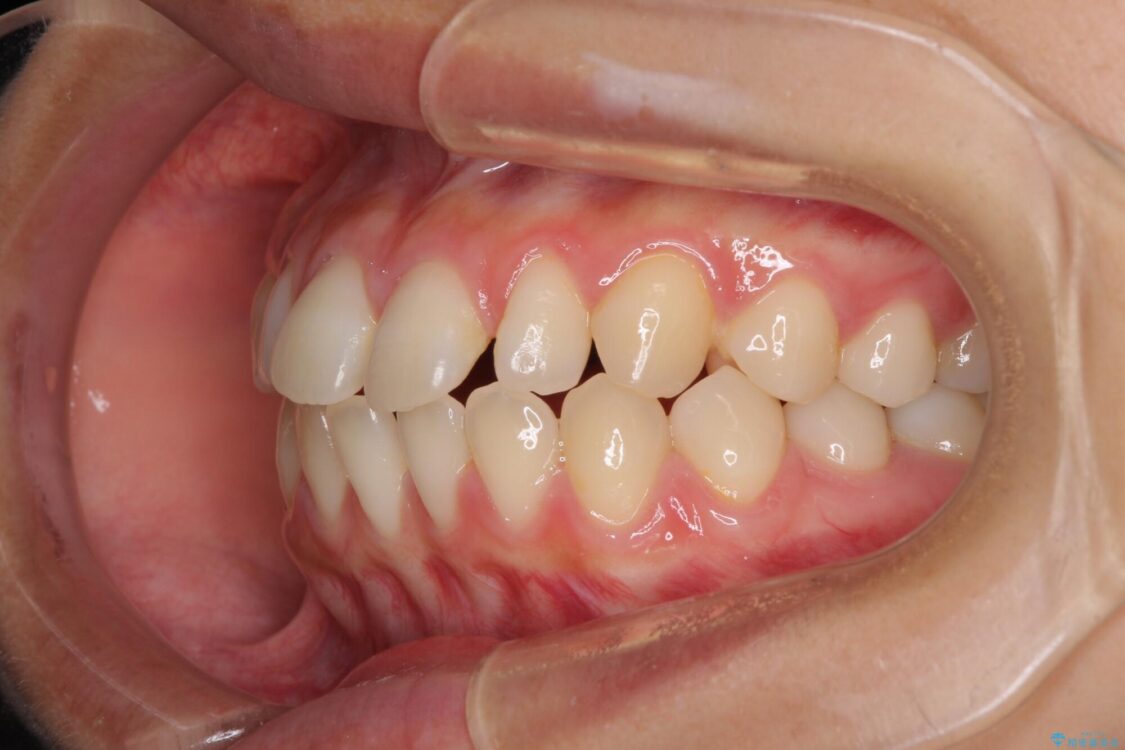

治療前

• 隙間だらけの歯列 インビザラインで改善 治療前画像